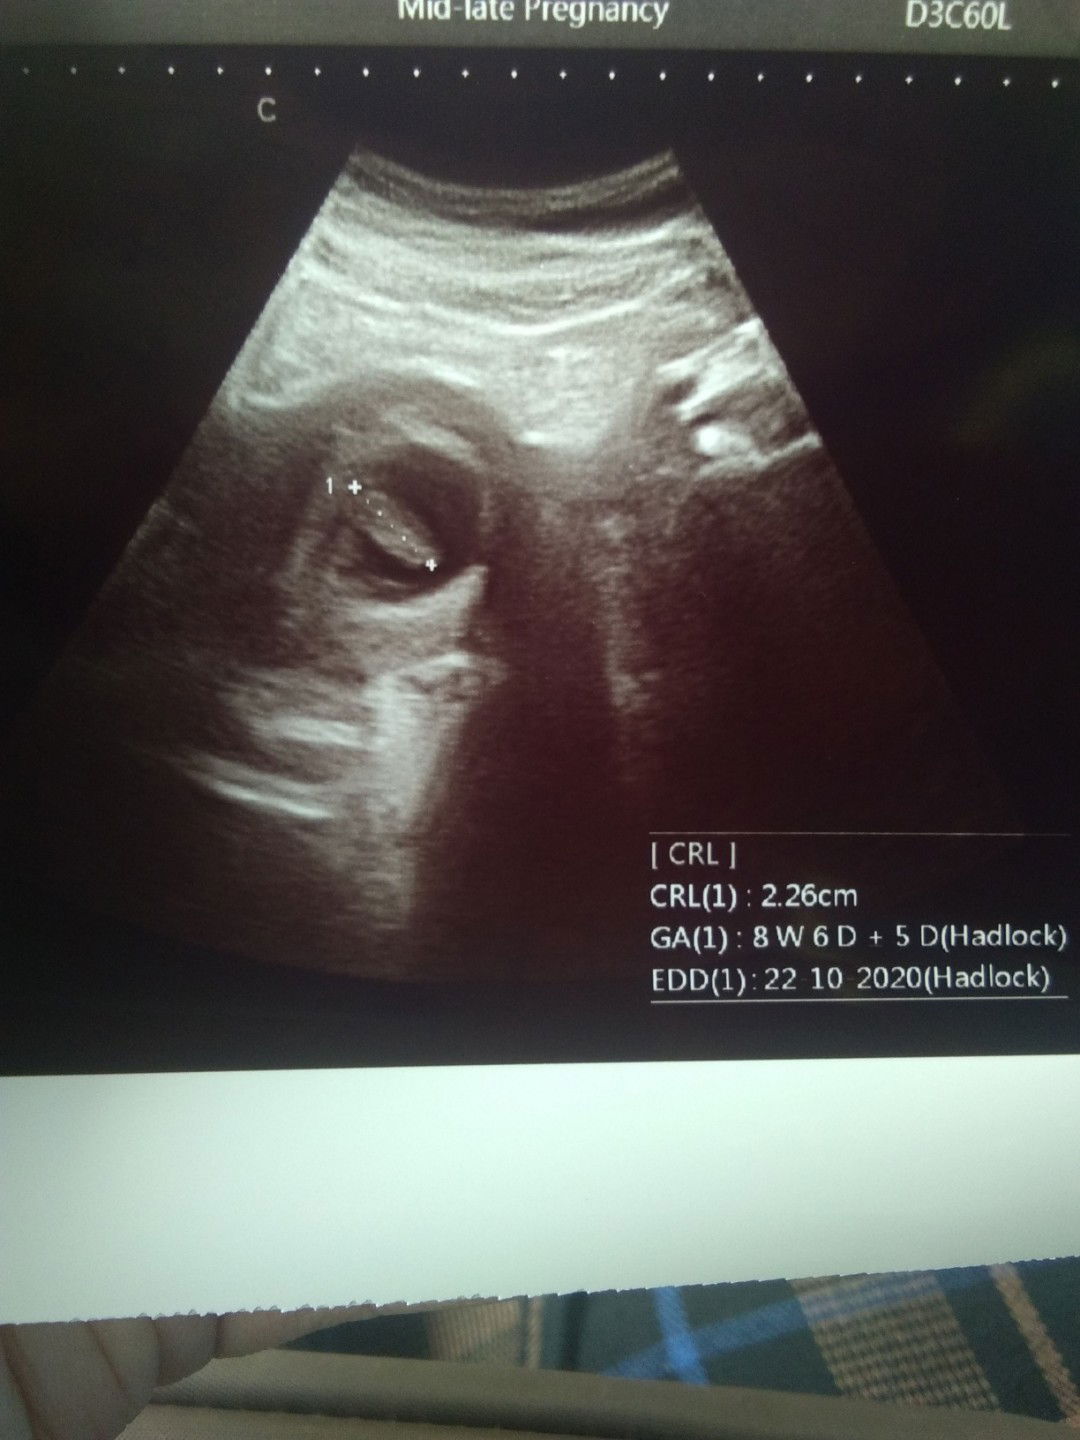

Hallo bunda bunda yang cantik. Sedikit cerita, dan semoga bisa memotivasi bunda bunda yang ngalamin pendarahan seperti yang aku rasakan. Lima minggu yang lalu alhamdulillah aku mendapatkan garis dua, tespack setelah telat haid 2 hari. Besoknya aku ke puskesmas, karena kondisi lagi demam, batuk pilek, sekalian periksa kehamilan. Waktu itu belum keraba dan disuruh balik lagi ke puskesmas 2 minggu kemudian. 2 minggu kemudian yang harusnya jadwal ke puskesmas, qodarullah pendarahan hebat, keluar gumpalan gumpalan darah persis kaya orang haid. Periksalah kita ke dokter kandungan, di USG alhamdulillah kantung janin masih ada. Kata dokter itu ancaman keguguran. Dikasih obat penguat kandungan dan vitamin. Bedrest total. 3 minggu lagi nanti harus kontrol, kecuali pendarahan keluar lg harus segera kontrol. Besoknya gumpalan itu masih ada lebih mirip kaya daging, besar. Udah stress, aku minta pulang ke kampung halaman, diijinin alhamdulillahnya. Kata bapakku, coba minum air kelapa kalau kantungnya masih ada mah, biar kandungannya kuat. Maksimal 2x seminggu. Dijalanin. Darah berhenti tapi masih ngeflek selama 9 hari. Suruh minum susu kambing, aku ikutin. Dan hari ini kontrol, deg degan takut aja bawaannya, belum siap kehilangan. Dan Alhamdulillah, qodarullah kandungan sehat, udah ada djj nya. Terharu masyaallah ☺. Buat bunda bunda yang flek yang pendarahan, semangat, tetep positif feeling. Semoga kandungannya baik baik aja. Oh iya, aku kadang suka ngelus perut dan bilang "yang sehat ya nak, yang kuat. Bunda ayah pengen ketemu kamu didunia. Kamu pengen kan nak ketemu bunda sama ayah?. Bunda yakin kamu kuat kok nak" Hehehehe ?